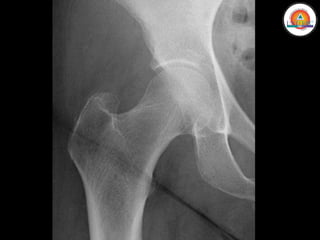

MIEMBRO INFERIOR

• Cintura pélvica

• Cadera

• Muslo (Fémur)

Huesos:

• Pelvis

• Fémur

MIEMBRO INFERIOR • Cinturapélvica • Cadera • Muslo (Fémur) • Rodilla • Pierna (Tibia y Peroné) • Tobillo • Pie (Tarso, Metatarso y Falanges)

MIEMBRO INFERIOR Huesos: • Pelvis •Fémur • Rótula • Tibia • Peroné • Tarso • Metatarso • Falanges